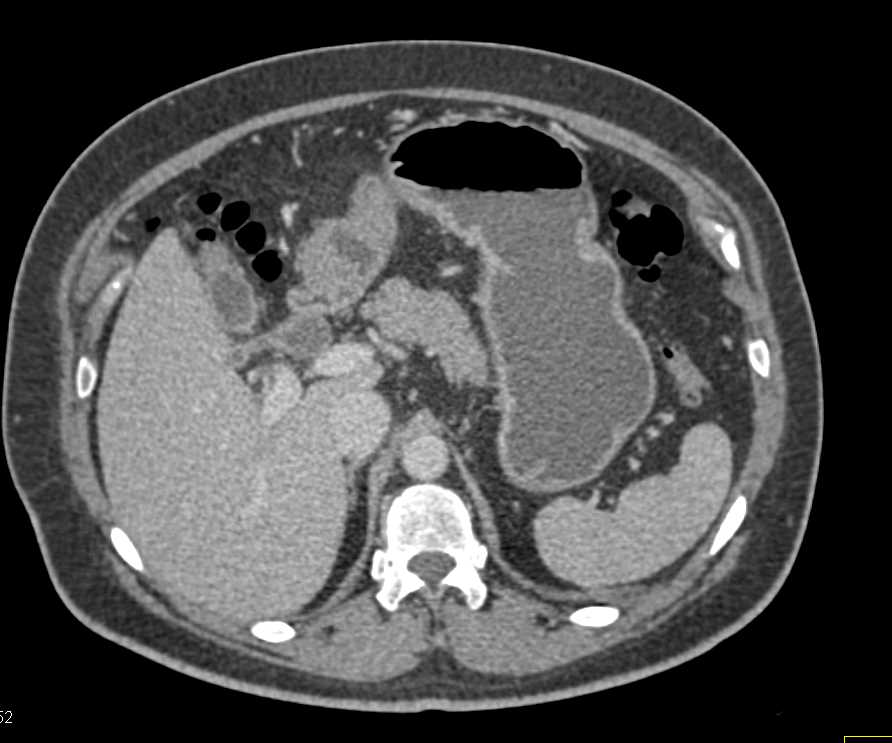

Professors Satomi Kawamoto and Professor Elliot K. Fishman (@ctisus), Associate Professor @LindaChuMD (@LindaChuMD), and Research Fellows Mohammad Yasrab and Juan Felipe Lopez-Ramirez (@FelipeLopezMD), presented an educational exhibit on βThe Challenges in the Detection and